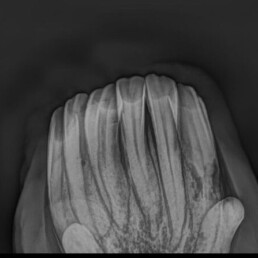

- röntgenologische Untersuchung zur Bestätigung der Verdachtsdiagnose EOTRH

- deutliche Befunde erkennbar

- resorptive und hyperzementotische Veränderungen an den Schneidezähnen/Schneidezahnwurzeln